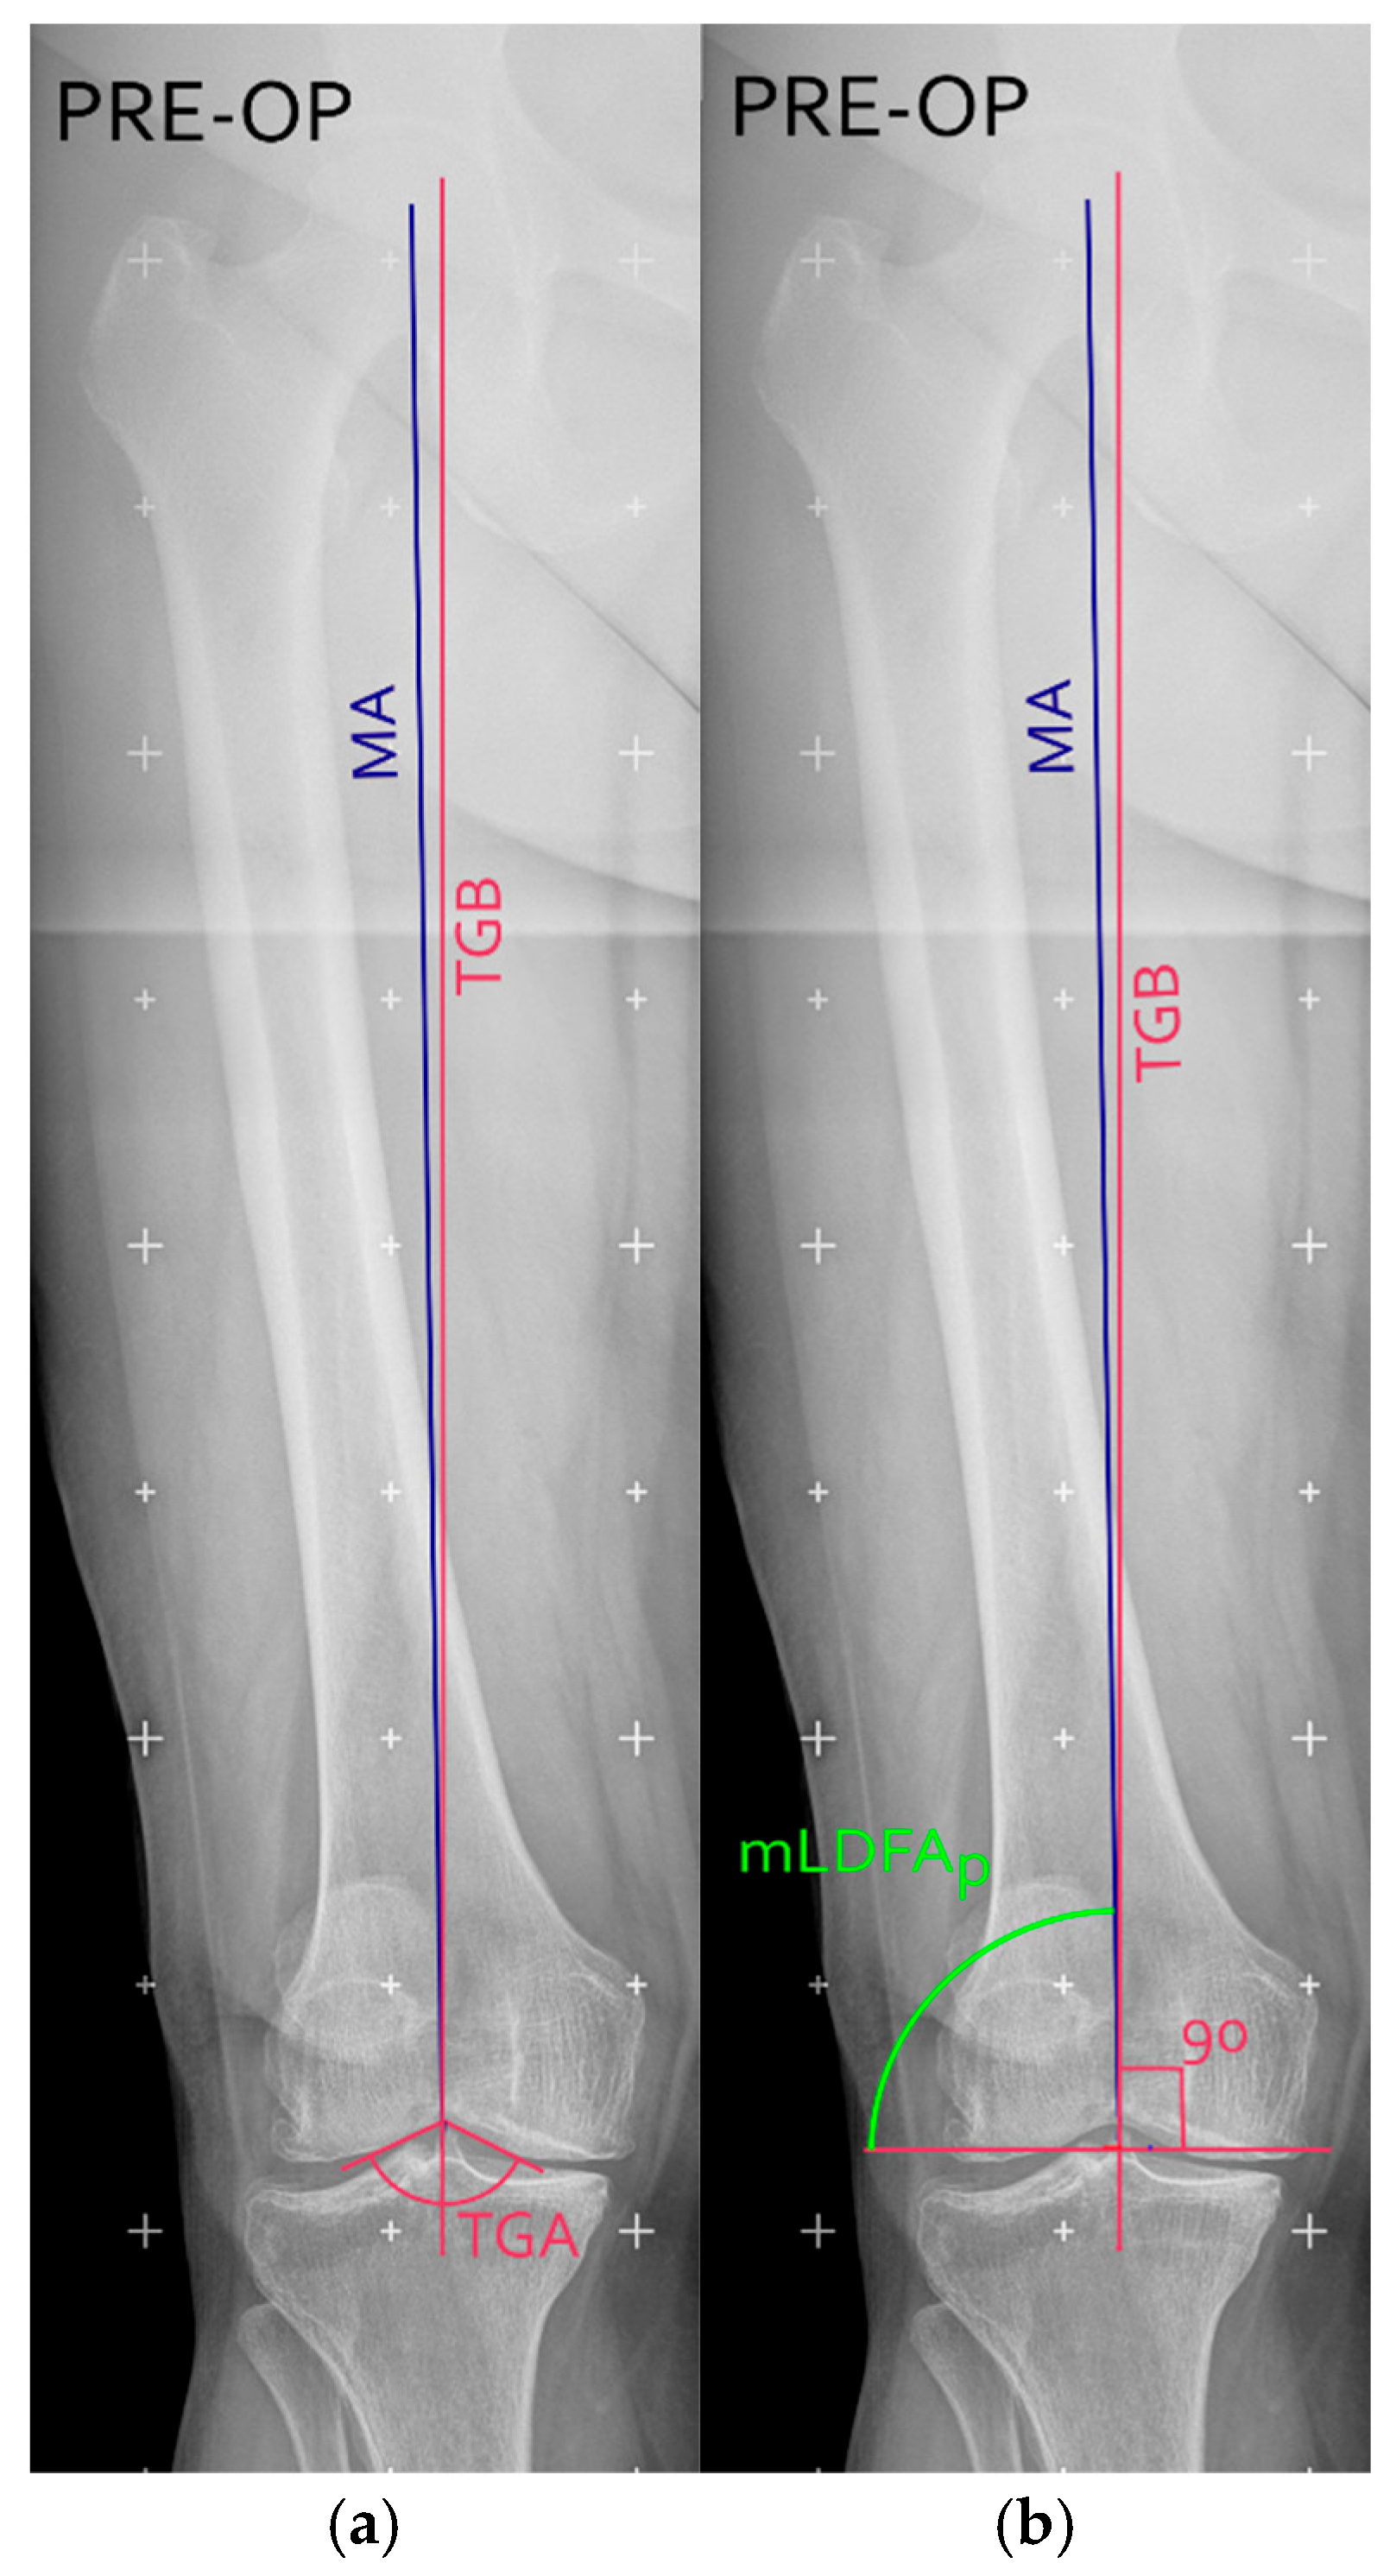

After the identification of bone landmarks, hip-knee angle (HKA), anatomical axis (AA), mechanical axis (MA), anatomical mechanical angle (AMA), and mechanical lateral distal femoral angles (mLDFA) were measured using standardized techniques to guide bone resections and implant positioning [20]. Also, the TGB was measured on long-leg coronal X-rays, as previously described [20]. In brief, the trochlear groove angle (TGA) was determined by drawing two tangential lines along the medial and lateral aspects of the trochlear groove from the radiographic apical midpoint of the intercondylar groove (see Figure 1a). The TGB was then drawn as the bisector of the TGA (purple vertical line in Figure 1a).

The distal femoral cut (purple horizontal line in Figure 1b) was planned perpendicular to the TGB. Once the distal femoral cut was identified, the MA was drawn and the planned mLDFA (mLDFAp) was defined as the angle between the planned cut and the MA [21].

Figure 1. Zoomed versions of the right knee in a pre-operative long-leg coronal X-ray, with the representation of the mechanical axis (MA, blue line); the trochlear groove bisector (TGB, purple line); trochlear groove angle (TGA) (a) and planned mechanical distal femoral (mLDFAp, green angle) (b). Figure created with Inkscape (version 1.4.3, The Inkscape Project, Boston, MA, USA).